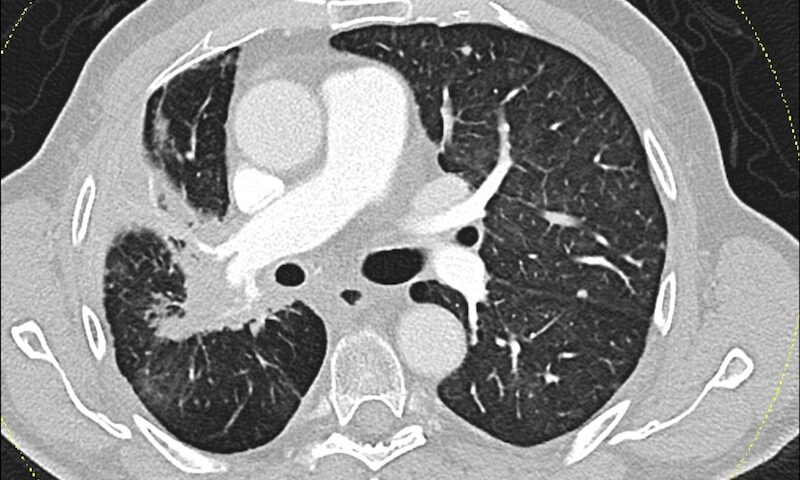

Lungenkrebs zählt weltweit zu den häufigsten Krebsarten mit hoher Sterblichkeitsrate. Für Patientinnen und Patienten mit nicht-operablem nicht-kleinzelligem Lungenkrebs (NSCLC) im Stadium III gilt die Kombination aus Chemotherapie und Bestrahlung (CCRT), gefolgt von einer Immuntherapie mit Durvalumab, als etablierter Behandlungsstandard – insbesondere bei positiver PD-L1-Expression (einem Protein auf Tumorzellen, das hilft, das Immunsystem zu umgehen). Diese Therapieform birgt jedoch Risiken: Sowohl die Strahlentherapie als auch die Immuntherapie können Entzündungen des Lungengewebes (Pneumonitis) auslösen. Aus diesem Grund wurde bisher meist eine Gesamt-Strahlendosis von 60 Gy nicht überschritten(Gy (Gray) ist die Maßeinheit für die auf Körpergewebe übertragene Strahlenmenge). Ein Forschungsteam an der KL Krems wollte nun herausfinden, ob eine höhere Dosis – und damit möglicherweise eine stärkere Tumorkontrolle – ohne zusätzliches Risiko möglich ist.

Insgesamt entwickelten 38,5 % der Teilnehmerinnen und Teilnehmer eine Pneumonitis, doch im 70 Gy-Kollektiv lag die Rate bei 34,5 %, im Vergleich zu 50 % in der Gruppe mit geringerer Dosis. Nur ein Fall einer schwerwiegenderen Pneumonitis (Grad 3) wurde beobachtet – und zwar in der niedrig dosierten Gruppe. Besonders deutlich zeigten sich Unterschiede beim Gesamtüberleben: In der Hochdosis-Gruppe lebten nach einem Jahr noch über 93 % der Patientinnen und Patienten – diese Rate blieb auch nach vier Jahren nahezu unverändert. Im Vergleich dazu lag das mediane Überleben in der Gruppe mit weniger als 70 Gy bei 31 Monaten, zudem traten dort häufiger Tumorprogressionen auf.

Strahlenbedingte Lungenschäden wurden vermieden, da die behandelnden Teams besonders auf eine exakte Planung geachtet hatten: Die mittlere Lungendosis (MLD) wurde in beiden Gruppen unter dem kritischen Wert von 20 Gy gehalten. „Solange man sich an die vorgegebenen Grenzwerte, vor allem im Niedrig-Dosis Volumen hält, sind keine höheren Pneumonitis Raten zu erwarten“, erklärt Dr. Schragel. „Die Ergebnisse zeigen: Eine höhere Dosis für den Tumor bedeutet nicht automatisch ein höheres Risiko für entzündliche Reaktionen der Lunge – wenn man richtig plant.“